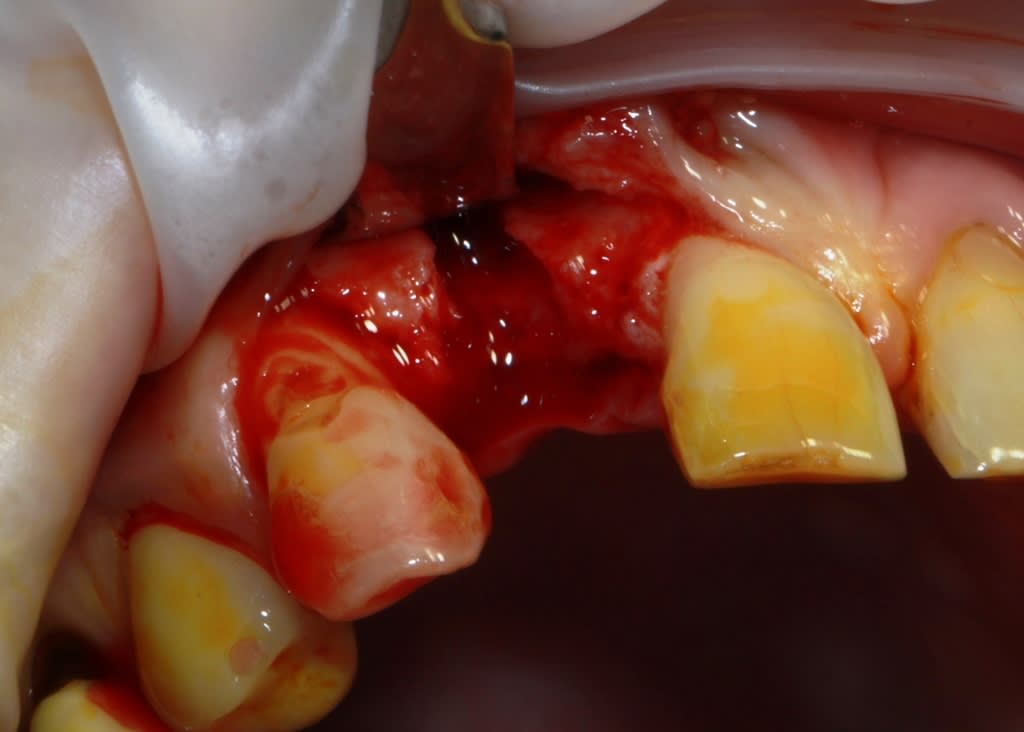

un petit cas comme j'aime, perte de 11, avec atteinte de la paroi vestibulaire.

Manipulation de la paroi palatine, afin de déplacer la moitié de l'os en vestibulaire, et pose d'un Px (Anthogyr) utilisation, de lame 11, ostéotome demi lune de Tatum, spreader (Meissinger) et divers.